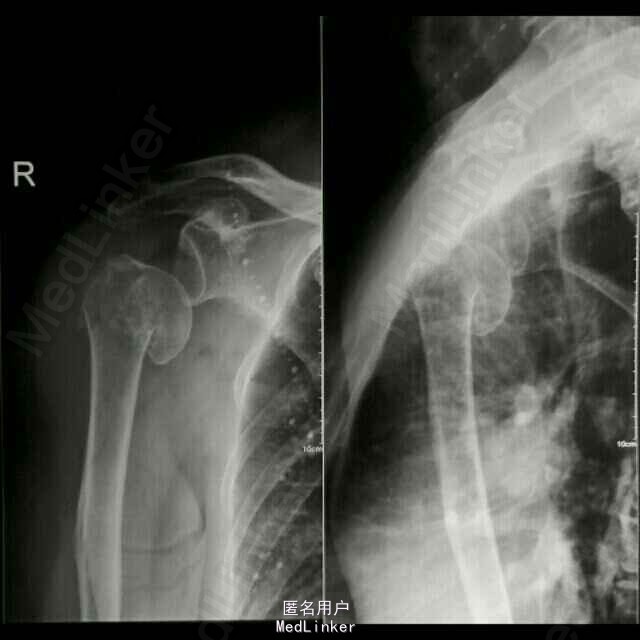

专科检查:右肩关节前内侧见一长约15cm的斜行手术疤痕,愈合良好,局部无红肿及压痛,右侧肩关节未见明显畸形,功能活动尚可,因上臂牵涉性疼痛活动受限,肩部无异常触痛;右上臂肿胀、畸形明显,皮肤张力稍高,局部假关节形成,局部皮肤无破损,未见明显挫伤痕迹,皮温正常,触痛明显,以右肱骨干中段处为甚,可扪及明显的骨摩擦感及异常活动;右肘关节无红肿及压痛,右肘关节伸直活动受限约30度,屈曲活动正常,右前臂活动正常;右上肢纵向叩击痛(++),患肢末梢循环、感觉、活动正常。 DR示:右侧人工肱骨头置换术后伴假体周围骨折,慢支炎肺气肿伴左侧胸腔积液。 颅脑MRI示:两侧基底节区陈旧性腔梗。

诊断:1、右侧人工肱骨头置换术后伴假体周围骨折 2、慢性肺气肿伴左侧胸腔积液 3、双侧脑基底节区陈旧性腔隙性脑梗塞灶 4、血压病(2级 高危层) 5、骨质疏松症(重度) 6、右髋关节置换术后 治疗: 因患者高龄,基础疾病较多,较重,故手术风险大,经呼吸内科,心血管内科及神经内科会诊及治疗处理后,患者内科病情控制稳定,予行手术治疗,术中检查,右肩关节假体无松动,故单纯予行假体周围骨折固定术治疗。